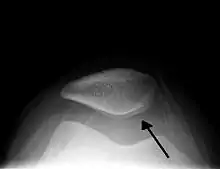

![]() انصباب في الركبة اليمنى نتيجة للإصابة. لاحظ الانتفاح الجانبي فوق الرضفة وكما مؤشر. انصباب في الركبة اليمنى نتيجة للإصابة. لاحظ الانتفاح الجانبي فوق الرضفة وكما مؤشر. | |

صورة توضح انصباب الركبة وكما مؤشر.